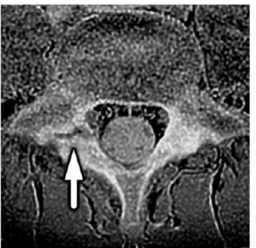

【画像:https://kyodonewsprwire.jp/img/202512030261-O4-1IWaCL03】

図2: 腰椎分離症のMR画像(画像は腰椎の水平断面を示す。矢印は腰椎分離症の病態箇所である)